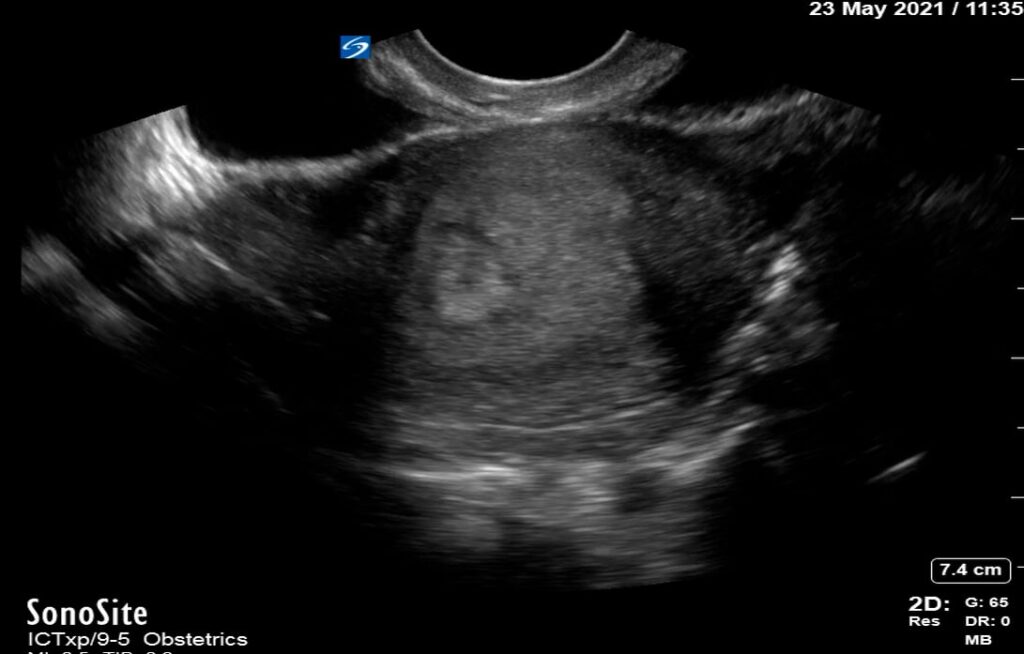

In OBGYN ultrasound, the yolk sac is a crucial early gestational structure, appearing as a small, round, anechoic fluid-filled sac within the chorionic cavity. Typically visible from 5-10 weeks of gestation, its presence confirms an intrauterine pregnancy and is a vital indicator of normal embryonic development. The yolk sac provides early nourishment to the embryo before the placenta fully forms.

Its proper visualization and size are important for dating the pregnancy and assessing viability. Abnormalities in yolk sac appearance, such as irregular shape or absent visualization when expected, can suggest potential complications or early pregnancy failure. Therefore, precise identification and evaluation of the yolk sac are fundamental for accurate diagnostic ultrasound in obstetrics.